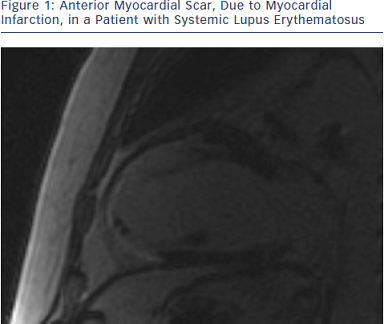

CMR is the most reliable imaging way to detect and quantify scar or fibrotic tissue, due to irreversible myocardial damage (viability study). Following acute ischaemic injury, the myocardial distribution volume of gadolinium is increased due to sarcolemmal rupture and abnormal wash-out kinetics. The preferred imaging time for scar detection is between 10 and 20 minutes after contrast agent administration, when the differences between scar, normal myocardium and blood pool are maximal. This method is referred in the literature as late gadolinium enhanced (LGE) CMR and is the gold standard for the in vivo assessment of myocardial scar (see Figure 1). CMR can detect infarction in as little as 1 cm3 of tissue, substantially less than other in vivo methods, such as echocardiography and nuclear techniques. Furthermore, CMR can detect subendocardial myocardial infarction, missed by SPECT/PET. The CMR extent of scar predicts the potential for functional recovery after revascularisation.36–38

Subendocardial and/or transmural LGE, following the distribution of coronary arteries, are indicative of CAD. However, not only the presence but also the LGE amount plays an important role in patients’ prognosis, because even a small area of LGE (<2 % of LV mass) was associated with a greater than seven-fold increase in risk for a major adverse cardiac event.39

LGE has already been described in vasculitis, myositis, SLE and RA; it may present different patterns including subendocardial or transmural lesions in the territory supplied by the occluded coronary artery, intra-myocardial or subepicardial not following the distribution of coronary arteries, mimicking the pattern of viral myocarditis and/or diffuse subendocardial pattern due to vasculitis.41